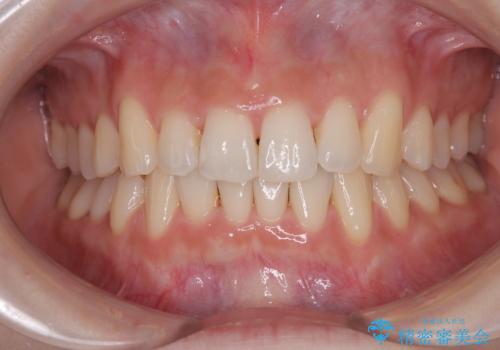

前歯が隠れるほどのデコボコをインビザライン矯正できれいに整える

マウスピース矯正特有の、奥歯が噛みにくくなるという現象の解消に少し期間をいただきましたが、日々の装着時間を遵守していただき、綺麗な歯列に整えることができました。